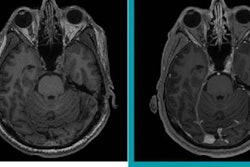

In addition, increased signal intensity in the deep cerebellar nuclei was evident 12 months later with linear GBCAs, while signal intensities were nearly comparable between rats given macrocyclic GBCAs and those receiving saline.

The rats given the linear GBCAs showed significantly higher DCN-to-brainstem signal-intensity ratios (p < 0.001) at all three time points, compared with the saline group. The ratios were similar between gadodiamide (mean, 1.37), gadopentetate dimeglumine (mean, 1.36), and gadobenate dimeglumine (mean, 1.36) and persisted over the course of the 52-week study.

On the other hand, there was no statistically significant difference (p > 0.42) in signal-intensity ratios between the macrocyclic GBCA rats and the saline group at any time point. At 52 weeks, the mean ratios were 1.27 for gadobutrol, 1.28 for gadoterate meglumine, 1.28 for gadoteridol, and 1.27 for saline.